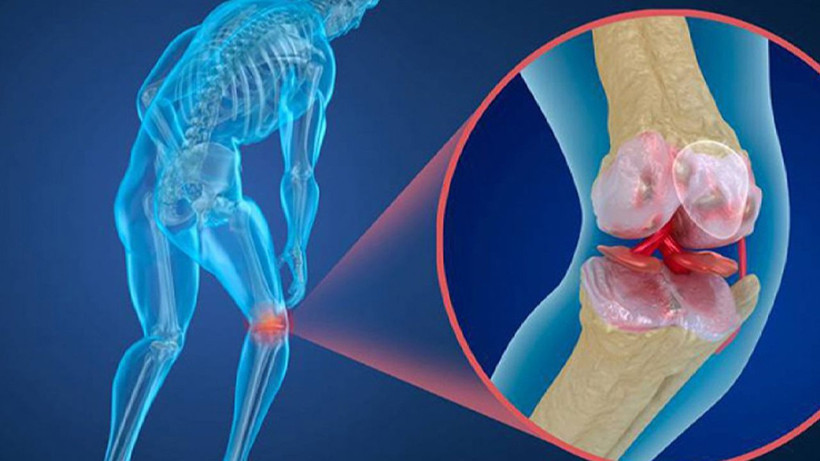

Kemik erimesi, kemiklerin mineral yoğunluğunun ve kütlesinin azalmasıyla karakterize edilen bir durumdur.

Kemik erimesi, kemik dokusunun kaybı ve mikro mimarideki değişiklikler nedeniyle kemiklerin zayıflamasına yol açar.

Kemik erimesinin başlıca nedeni, vücudun kalsiyum ve fosfor gibi mineralleri yeterince emmemesi veya koruyamamasıdır. Bu, genellikle hormonal değişiklikler, yaşlanma, hormonal bozukluklar veya genetik faktörlerle ilişkilidir.